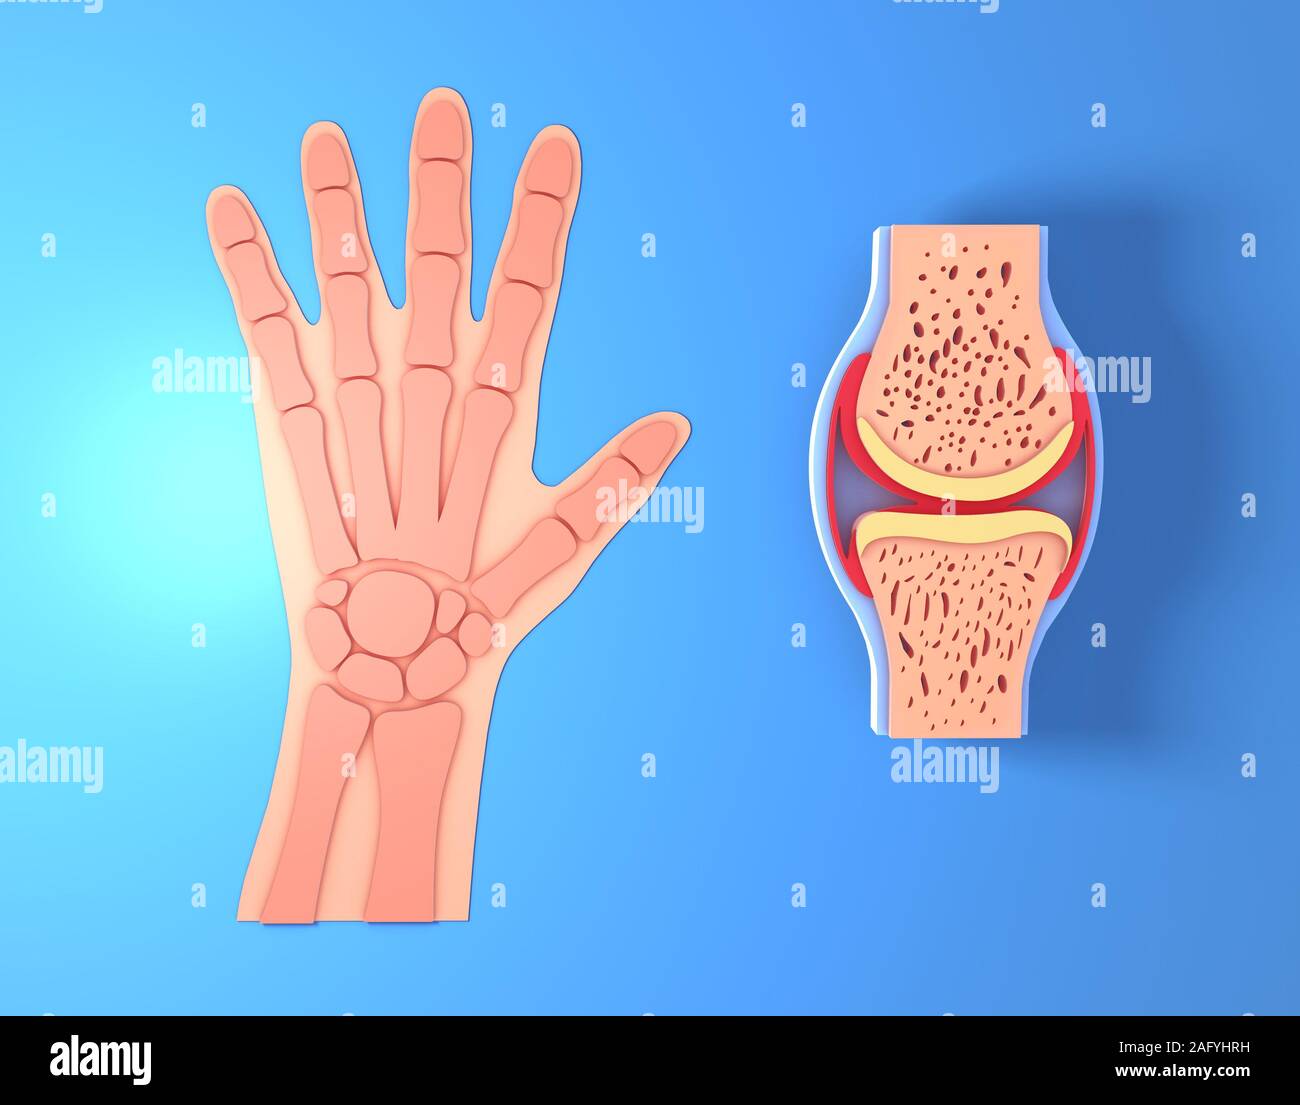

3d illustration of synovial joint. Next to the graphic representation of a hand placing the joint, front view on blue background. Stock Photohttps://www.alamy.com/image-license-details/?v=1https://www.alamy.com/3d-illustration-of-synovial-joint-next-to-the-graphic-representation-of-a-hand-placing-the-joint-front-view-on-blue-background-image336823525.html

3d illustration of synovial joint. Next to the graphic representation of a hand placing the joint, front view on blue background. Stock Photohttps://www.alamy.com/image-license-details/?v=1https://www.alamy.com/3d-illustration-of-synovial-joint-next-to-the-graphic-representation-of-a-hand-placing-the-joint-front-view-on-blue-background-image336823525.htmlRF2AFYHRH–3d illustration of synovial joint. Next to the graphic representation of a hand placing the joint, front view on blue background.